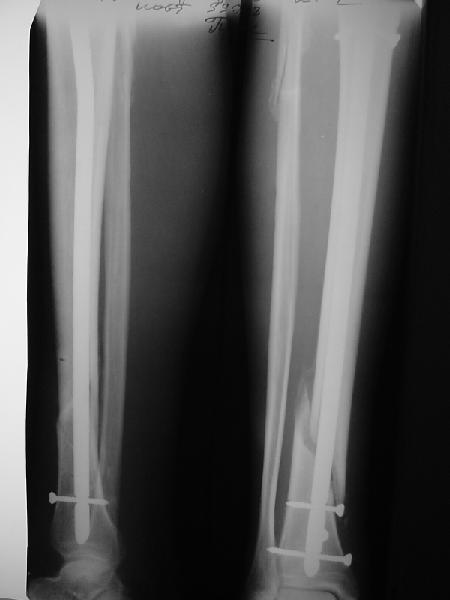

По крайней мере ходящих без дополнительной опоры через 1 месяц после операции с небольшой - при изолированной травме немало. Нестабильные по оси, кстати, не только оскольчатые, но и спиральные.

И если пациент еще не возвращается к полной нагрузке и функции, то не потому, что не разрешает врач, опасаясь несостоятельности фиксации.

Как мне показать пример? Фото стоящего на одной оперированной конечности пациента? O! Пример, подвигнувший нас на некоторое изменение технологий. Пациент этот ходил с полной нагрузкой вопреки рекомендациям. В качестве подтверждения - сломанный проксимальный статический винт к 1 мес., а к 2 мес. - все остальные. Сейчас мы перешли на более fool-proof остесинтез.

На мой взгляд, на снимках, приведённых Вами - неправильно сростающийся перелом дистальной трети большеберцовой кости, состояние после остеосинтеза интрамедуллярным гвоздём.

Как Вы пишите снимок под номером 1 - менсяц после операции, под номером 2- два месяца после операции.